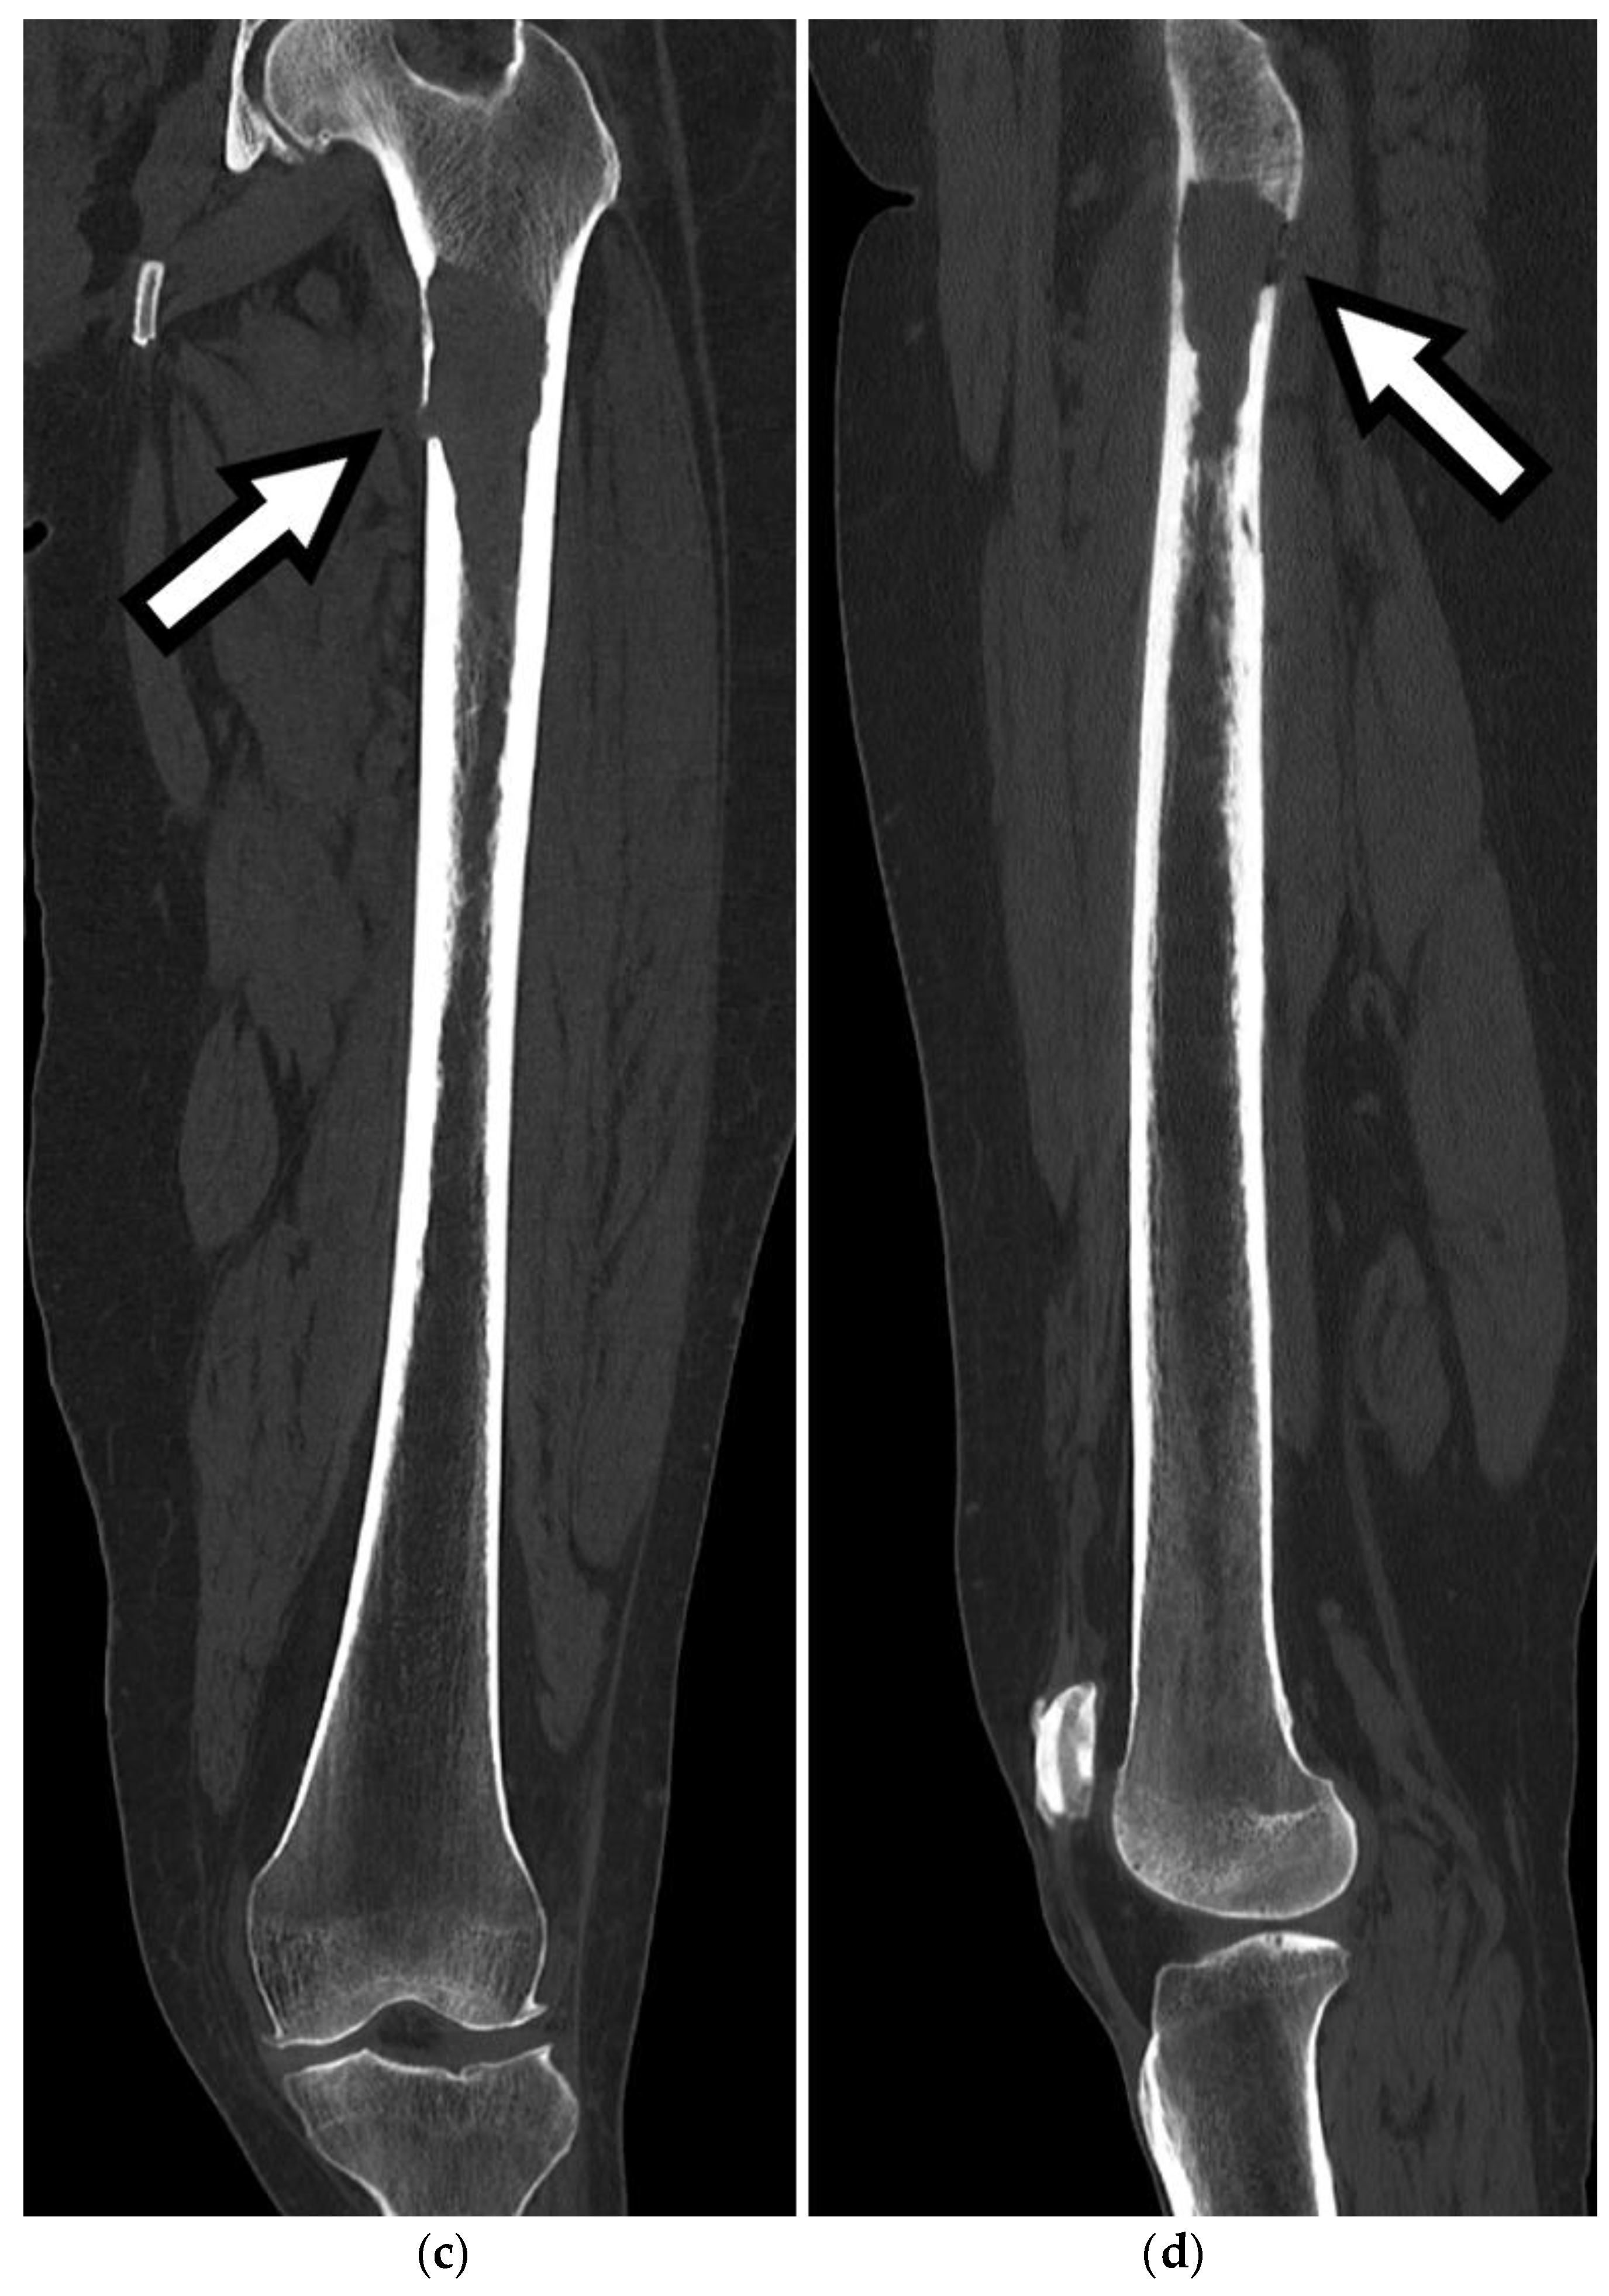

Figure 4. Axial (a,b), coronal (c), and sagittal (d) CT images show a destructive lytic lesion in the left proximal femoral metaphysis and diaphysis with cortical breakthrough both medially and posteriorly, concerning for pathologic fracture secondary to multiple myeloma.

CT imaging plays a vital role in the evaluation and management of FSFs by providing detailed information on the fracture pattern, displacement, intra-articular extension, and associated injuries, as seen in Figure 3 and Figure 4. Furthermore, Figure 5 demonstrates an example of a 3D reconstruction CT for surgical planning. The precise visualization of these key CT findings assists orthopedic surgeons in fracture classification, treatment planning, and surgical decision making. Incorporating CT imaging into the diagnostic workup of FSFs enhances the accuracy of diagnosis and contributes to improved patient outcomes.